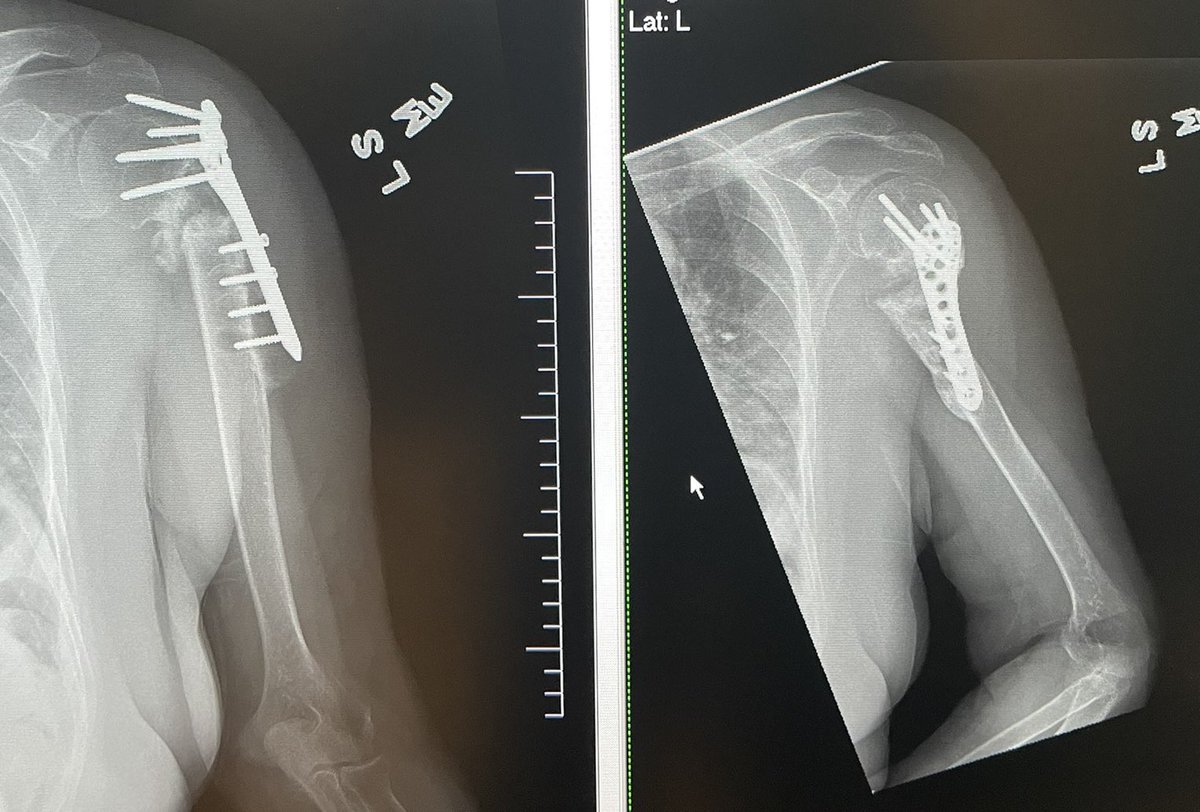

8 months post Left proximal humeral nonunion repair with revision ORIF and RIA reamer. That humeral head was definitely worth saving! 👍🤗#orthotwitter #Limblengthening #OTA #nonunion

JanetConwayy's tweet image. 8 months post Left proximal humeral nonunion repair with revision ORIF and RIA reamer. That humeral head was definitely worth saving! 👍🤗#orthotwitter #Limblengthening #OTA #nonunion